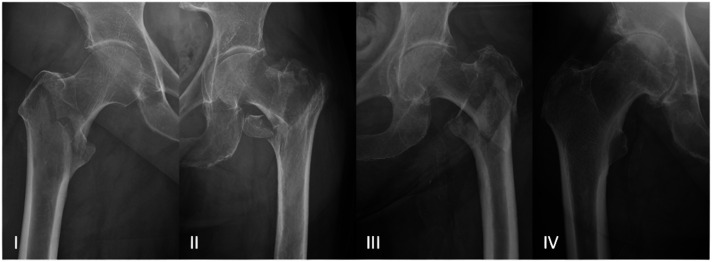

Methods: In this retrospective single-center study elderly patients aged ≥70 years who underwent intramedullary nailing between January 2016 and March 2023 have been analysed. The severity of hip osteoarthritis was stratified into two categories: grade 0-II and grade III-IV, according to the Kellgren-Lawrence classification system. Radiological signs of consolidation were ascertained. A comprehensive evaluation of the patients' demographics and patient-reported outcome measures (Oxford Hip Score, WOMAC-score, and SF-36-score) was conducted, followed by a thorough statistical analysis, with a significance set at P < 0.05.

Results: 21 patients with 23 affected hips were included (mean age 81 ± 7.5 years; 81% female) with a mean follow-up duration of 15.1 ± 13.8 months. Patients with advanced OA (KL III-IV) reported significantly lower Oxford Hip Scores (33.3 ± 6.3 vs 43.1 ± 6.7; P = 0.003), and higher total WOMAC and WOMAC pain scores (P = 0.016 and P = 0.003).